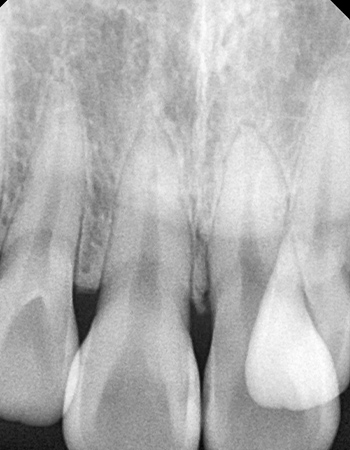

논문 발췌 사진